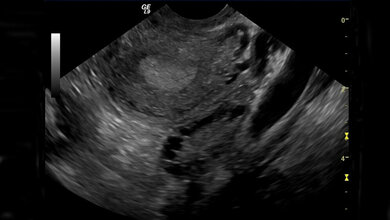

Der Eierstockkrebs ist eine aggressive Tumorerkrankung, die in der Regel erst im Spätstadium entdeckt wird. Bei Frauen ist er die fünfthäufigste krebsbedingte Todesursache. Neue Therapieoptionen sind daher dringend notwendig.

Die vorliegenden Forschungs-Ergebnisse sind insbesondere das Resultat einer intensiven interdisziplinären Zusammenarbeit zwischen dem IMT sowie der Klinik für Gynäkologie der Philipps-Universität. Die räumliche Nachbarschaft der jeweiligen Laboratorien im Marburger ZTI förderte einen schnellen Austausch. Zudem entwickelten die Forschungs-Teams ein Konzept zur engen Verzahnung von Klinik und Forschung. Konkret: Nach der Krebs-Diagnose leiteten die Ärzte am Universitätsklinikum Marburg die Behandlung ein – in der Regel eine operative Entfernung des Tumor-Gewebes. Dabei wurde auch der Aszites mit Einverständnis der Patientin in die ZTI-Labors übermittelt, dort aufgearbeitet und detaillierten Analysen unterzogen. Der Aszites ist besonders wertvoll als Untersuchungsmaterial, da es sehr viele Tumor- und Immunzellen enthält und so Forschungsarbeiten mit einem direkten klinischen Bezug ermöglicht: „Ein herausragendes Beispiel fachübergreifender Zusammenarbeit zwischen klinischen und grundlagenorientierten Forschern“, betont Sabine Müller-Brüsselbach.